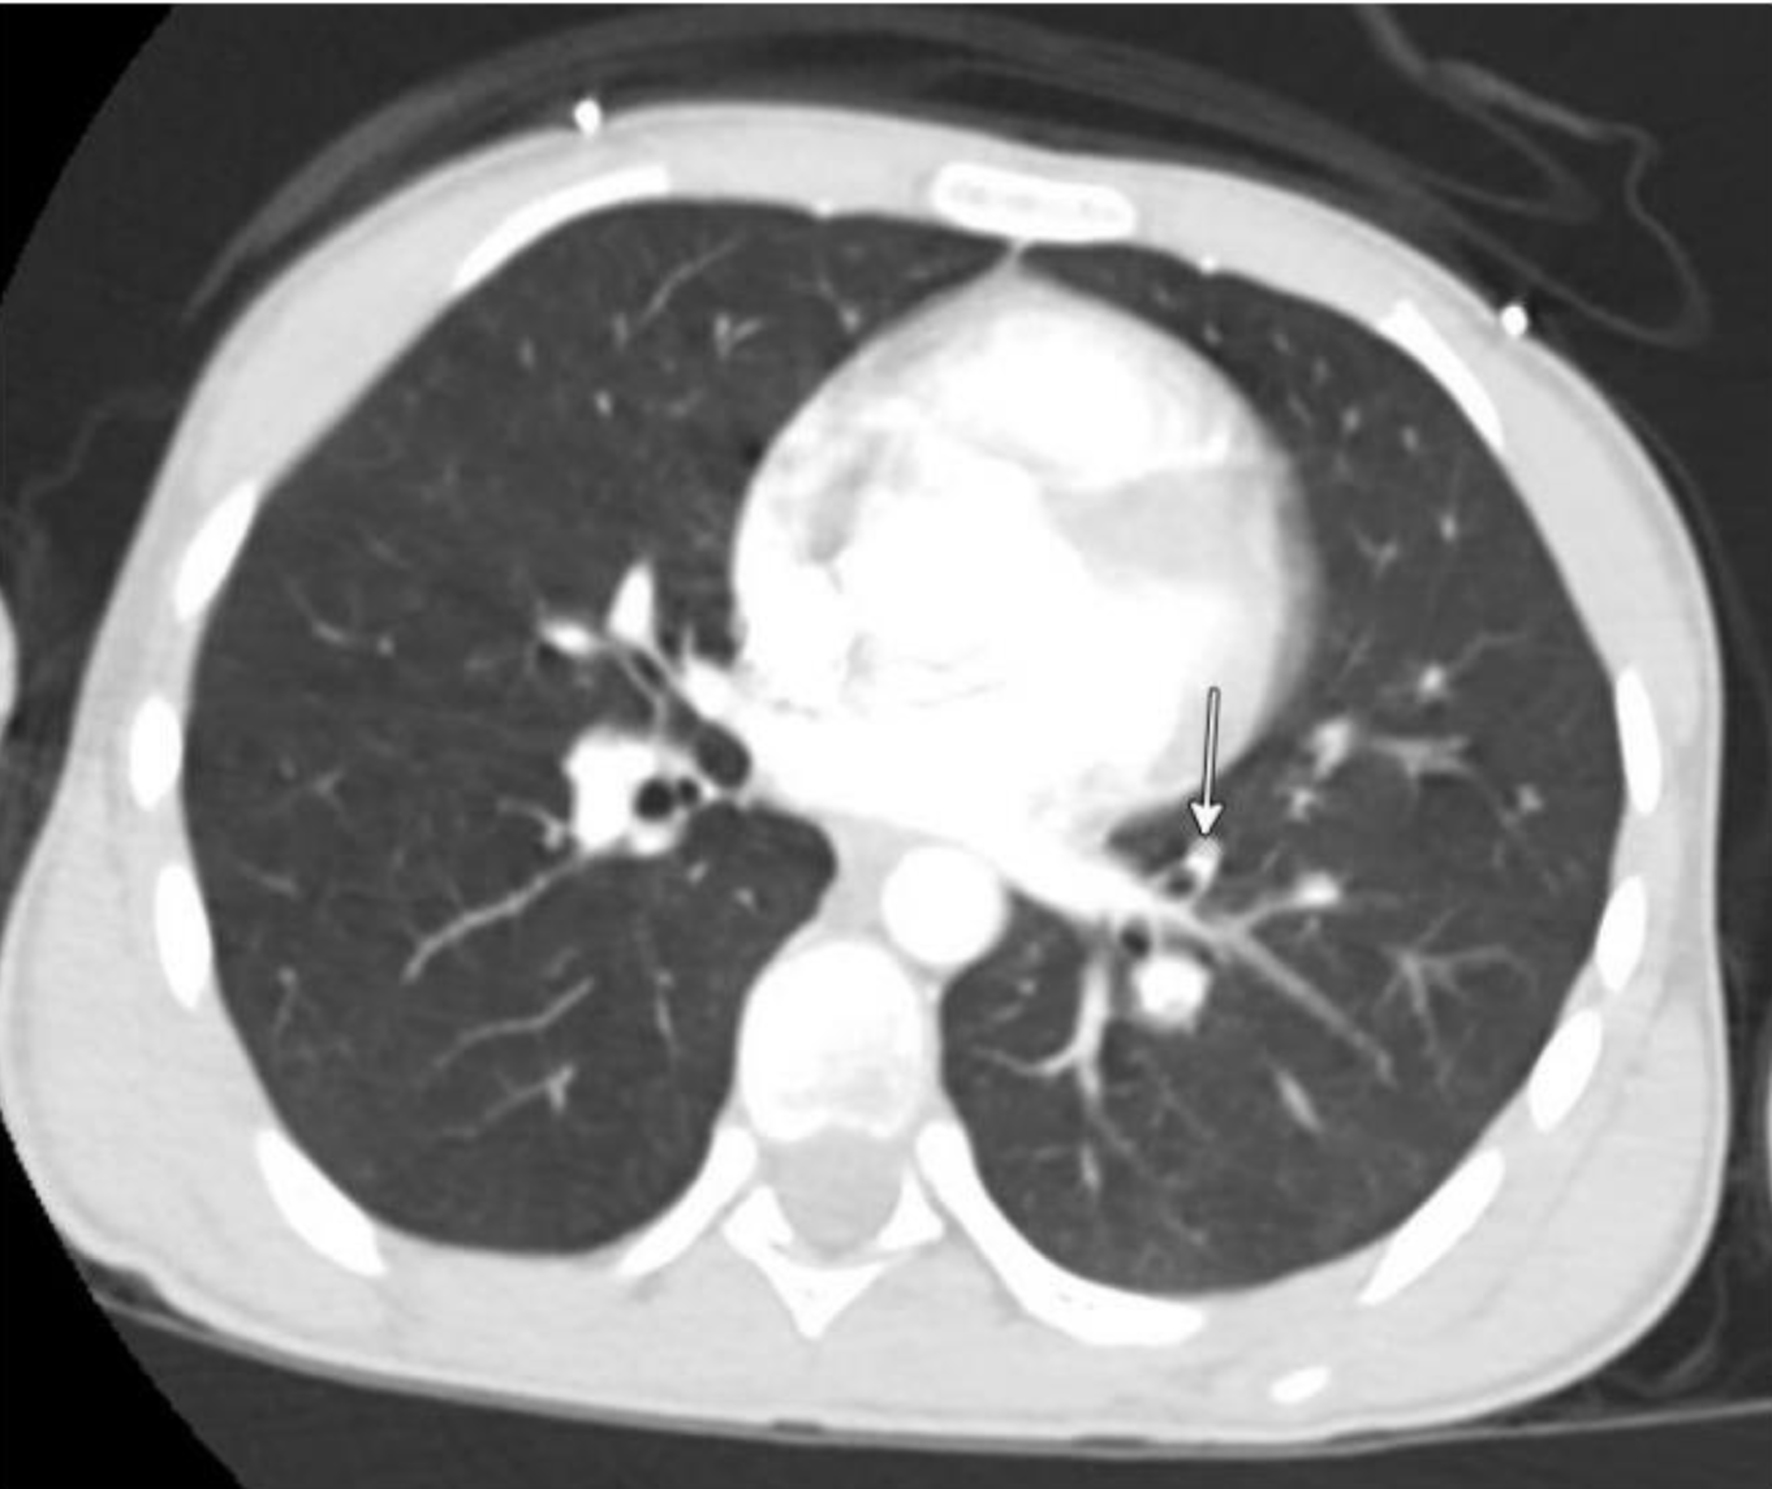

On hospital day 6, the patient underwent a second thrombectomy in interventional radiology (Fig. 2). Intraoperatively, a continuous bivalirudin infusion was infused at 0.5 mg/kg/h and titrated sequentially to 0.6 mg/kg/h, 0.75 mg/kg/h, and finally reduced to 0.15 mg/kg/h at the completion of the procedure. Intraoperative monitoring of activated clotting time (ACT) was used to guide dosing adjustments. Pharmacochemical and suction thrombectomy was performed via right internal jugular and posterior tibial vein access. A large volume of acute thrombus was removed with restoration of in-line flow. Both internal iliac systems were noted to be occluded, but no IVC thrombus was seen.

Click for large image

Figure 2. Fluoroscopic image from interventional radiology showing thrombotic occlusion of the internal iliac vein.